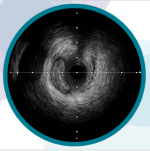

石灰化病変におけるステント拡張を予測するIVUSカルシウムスコア

野口 将彦 先生(東京ベイ・浦安市川医療センター 循環器内科)